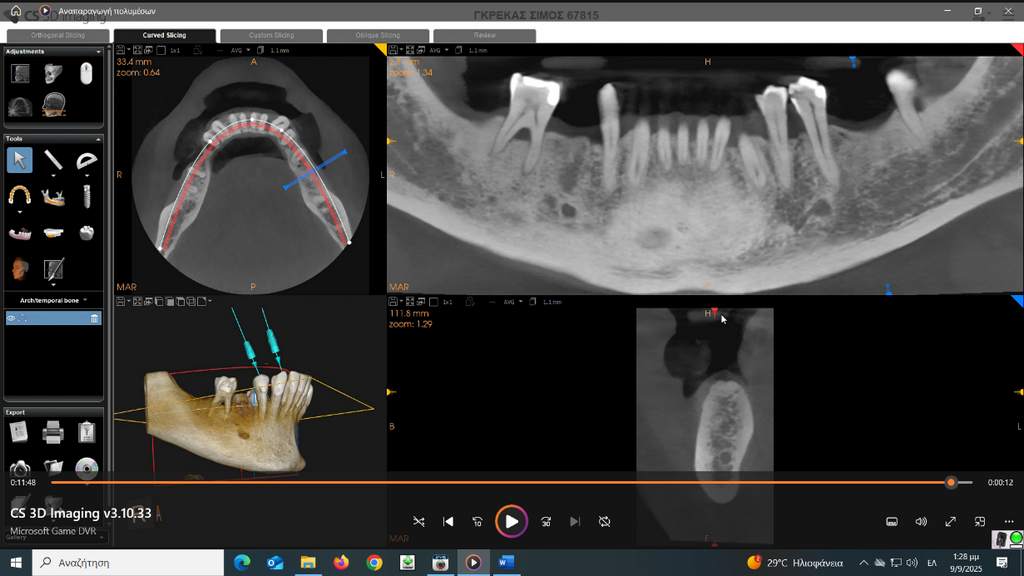

Σήμερα, στο «οπλοστάσιό» μας, έχει προστεθεί και η υπολογιστική τομογραφία κωνικής δέσμης (CBCT), οι εικόνες της οποίας είναι ιδανικές τόσο για να μας πληροφορήσουν για τη μορφολογία του συστήματος των ριζικών σωλήνων αλλά κυρίως να μας βοηθήσουν στη διάγνωση των βλαβών στο άκρο της ρίζας, στην έκταση αυτών των βλαβών και τη σχέση τους με παρακείμενες ανατομικές δομές (π.χ. ιγμόρειο).